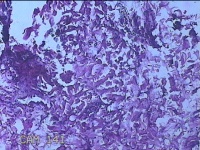

左前臂结节

性别

女

年龄

46岁

临床诊断

皮脂腺囊肿

一般病史

发现左前臂结节4个月余,无明显疼痛及不适。

标本名称

大体所见

灰白暗红色组织1.3x0.8x0.3cm一块,表面带梭形皮肤1.2x0.3cm,皮下见结节1x0.8x0.3cm一个,切开结节呈实性,切面灰白粉红色,质软。